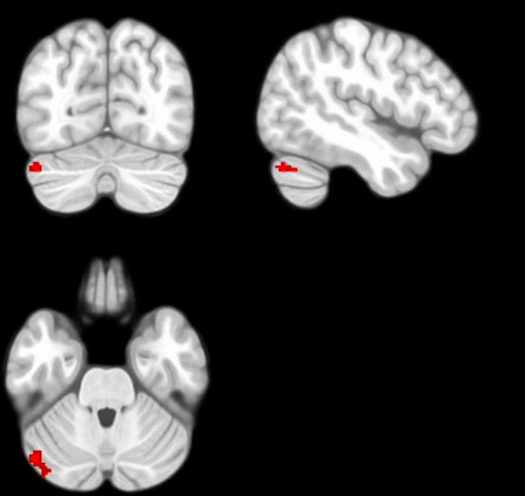

Compared with HCs, patient with CI showed increased fALFF in left cerebellum crus 1 (Figure 1). The seed-based FC analysis showed that left cerebellum crus 1 showed increased FC with right cerebellum crus 1 in patients with CI than HCs (Figure 2). The fALFF and FC values were positively correlated with symptom scores measured by CISS and NPC, and negatively correlated with horizontal phoria at near (PAN) and PFV (Tables 1 and 2).

Figure 2. Seed-to-voxel analysis showed greater functional connectivity of the left cerebellum crus 1 with the right cerebellum crus 1 in CI patients than HCs. P < 0.05, p-FWE corrected.